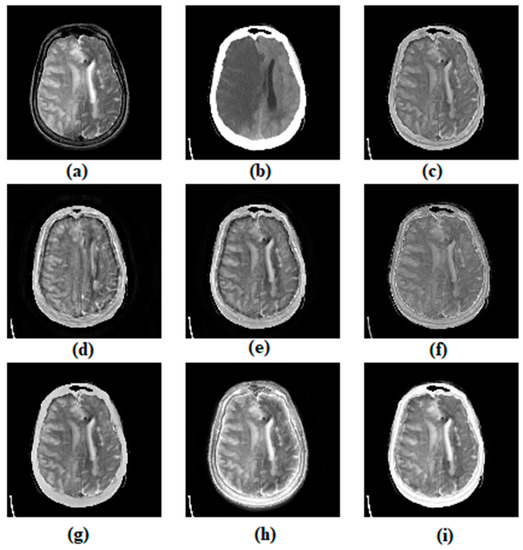

3.1. Subjective Assessment

| Metrics | Methods | ||||||

|---|---|---|---|---|---|---|---|

| ASR | CVT | DTCWT | MSVD | CSMCA | NSST | Proposed Method | |

| EI | 51.347 | 63.877 | 58.355 | 49.732 | 51.899 | 65.474 (2) | 65.802 (1) |

| MI | 4.186 | 3.878 | 3.995 | 4.090 | 4.284 (2) | 4.214 | 4.549 (1) |

| VIFF | 0.356 | 0.362 | 0.365 | 0.348 | 0.412 (2) | 0.340 | 0.484 (1) |

| 0.465 (2) | 0.418 | 0.431 | 0.380 | 0.461 | 0.446 | 0.478 (1) | |

| SSIM | 0.674 (2) | 0.338 | 0.507 | 0.417 | 0.663 | 0.590 | 0.694 (1) |

| AG | 5.065 | 6.231 | 5.719 | 5.197 | 5.045 | 6.349 (1) | 6.326 (2) |

| RMSE | 0.028 | 0.029 | 0.029 | 0.026 | 0.028 | 0.022 (2) | 0.018 (1) |

| PSNR | 17.396 | 17.268 | 17.649 | 16.392 | 18.644 (1) | 14.096 | 18.024 (2) |